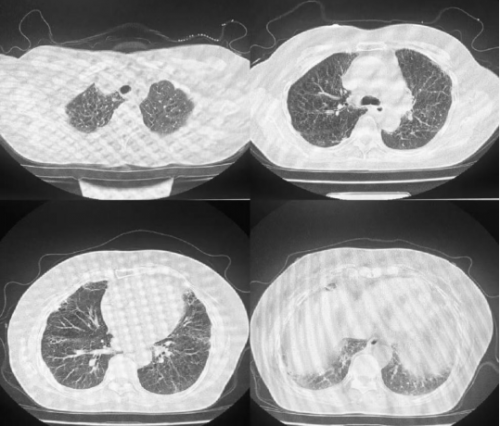

CT 影像:11 月 27 日复查胸部 CT,可见双肺磨玻璃渗出影明显吸收,对比 11 月 18 日影像,肺部病变改善显著。

11月27日肺CT:

11月18日肺部 CT

11月27日肺部CT